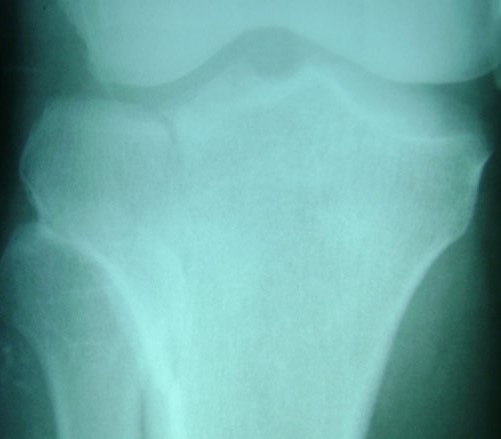

PRESENCIA DE ANEURISMA QUE COMPROMETE LAS ARTERIAS CEREBRALES.